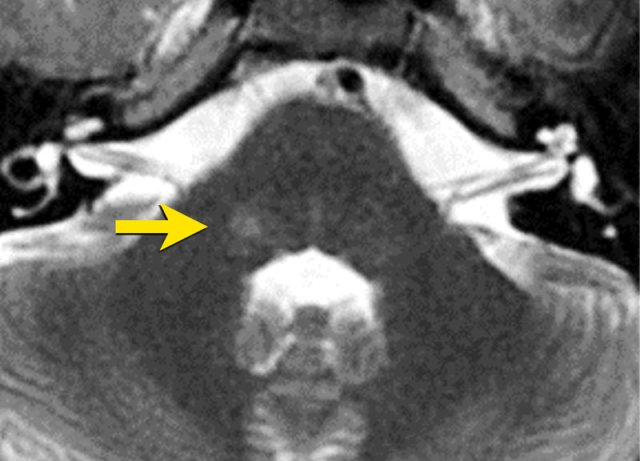

This image is of a 26 year old male who developed slowly progressive facial hypesthesy on the right.

The axial T2W image shows a hyperintense lesion at the trigeminal nucleus (arrow).

This may be a sign of demyelinsation, for instance in multiple sclerosis